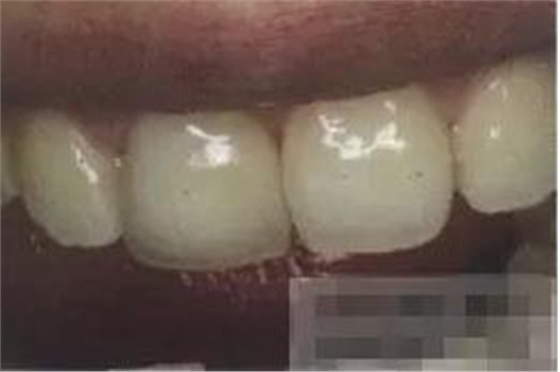

【檢查】12,11,21,22,均行玻璃離子充填,各牙不同程度部分充填物脫落,探(—),叩(—),冷刺激無(wú)反應(yīng),無(wú)松動(dòng),牙齦顏色粉紅,質(zhì)地堅(jiān)實(shí)而有彈性,點(diǎn)彩正常,牙結(jié)石(—);牙髓活力測(cè)試無(wú)反應(yīng)。

【診斷】12,11,21,22牙體缺損